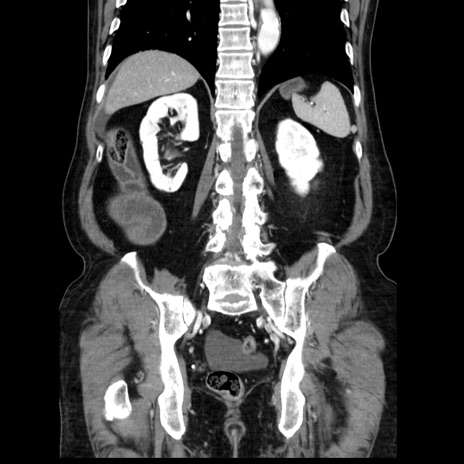

症例30(冠状断像)

【症例】80歳代男性

【主訴】臍周囲痛

【現病歴】約6時間前から臍下部痛が出現。次第に腹部膨隆・背部痛も生じてきたため来院。背部痛の場所は変化しない。

【身体所見】意識清明、BT 36.3℃、BP  131/87mmHg、P 87bpm、SpO2 100%(RA)、臍周囲自発痛・圧痛あり、反跳痛なし、自発痛部位に一致して板状硬あり、腹部膨隆、腸雑音減弱、CVA tenderness両側陰性。

【データ】WBC 19600、CRP 0.33